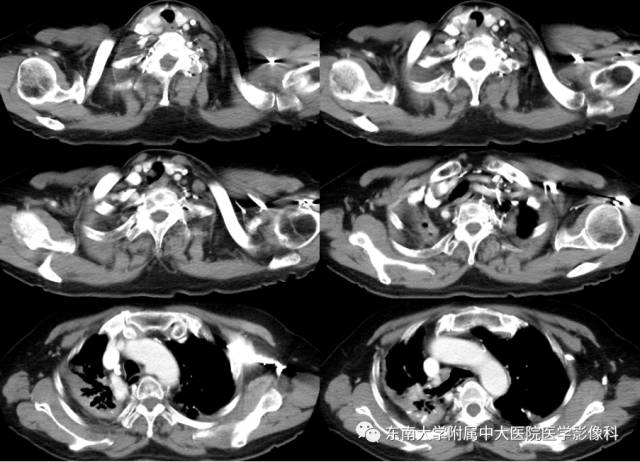

病例2

病史

女,65岁,因“气喘、气促半年余”入院。

CT

增强